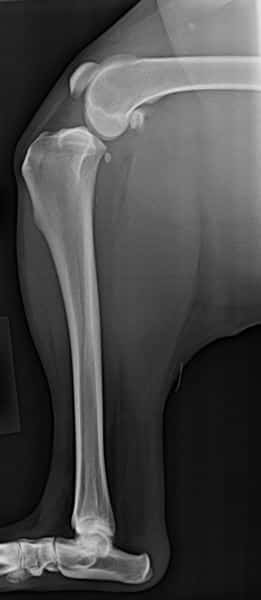

The Cranial Cruciate Ligament (CCL) is a crucial component of your dog’s knee joint, providing essential stability. Unfortunately, CCL rupture is one of the most common and painful knee injuries in dogs, particularly in medium to large breeds that are active. When the Cranial Cruciate Ligament is torn, it causes significant instability in the knee, leading to severe pain and discomfort.

If a CCL tear is left untreated, it can result in irreversible knee damage, including arthritis, which can impact your dog’s quality of life permanently. Surgery is the only effective treatment for Cranial Cruciate Ligament injuries, as it corrects the instability and helps prevent the long-term development of arthritis. Understanding the importance of the CCL and recognizing the signs of a tear can ensure your dog receives the necessary care to maintain a healthy, active lifestyle.

Before TPLO